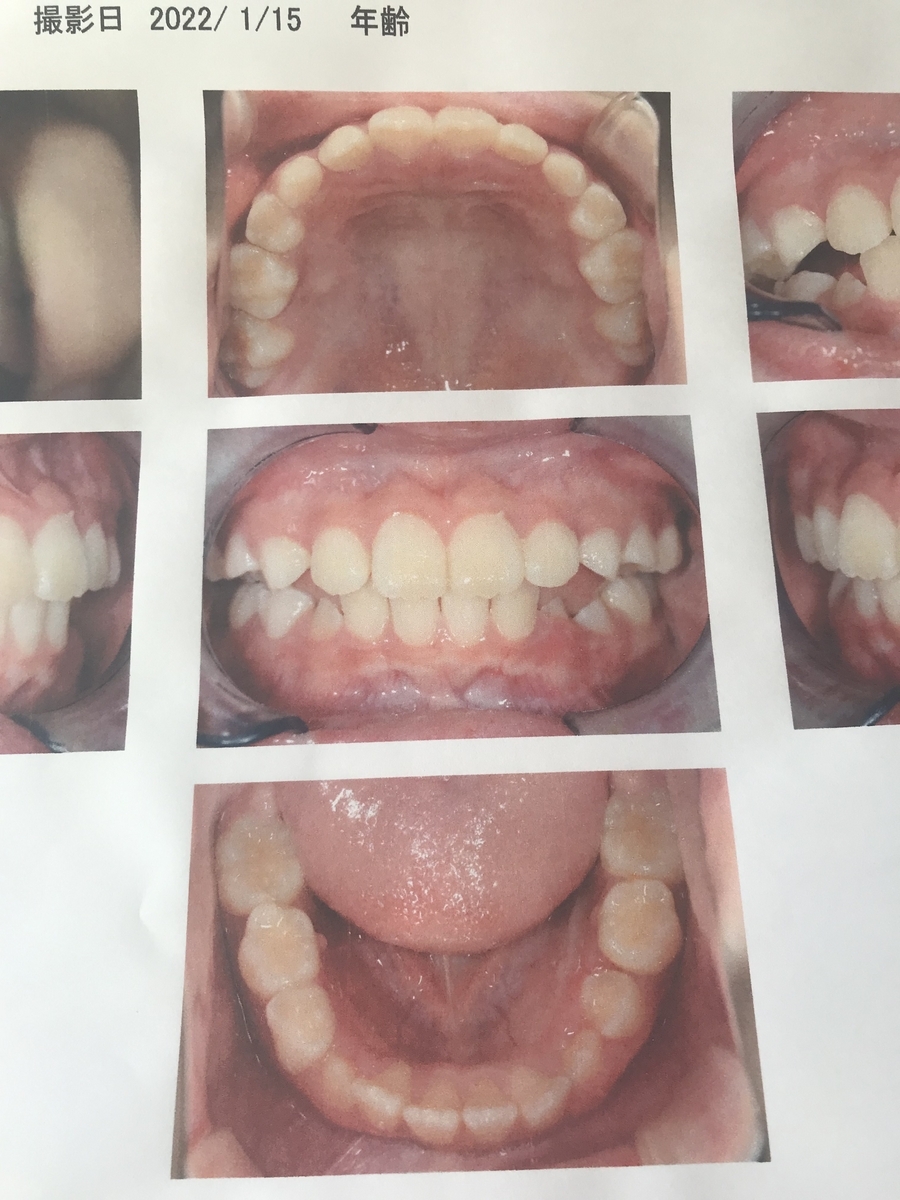

2022年8月(5年生)

どんどん永久歯に生え変わる時期で、針金が引っかからなかったり色々ありました。